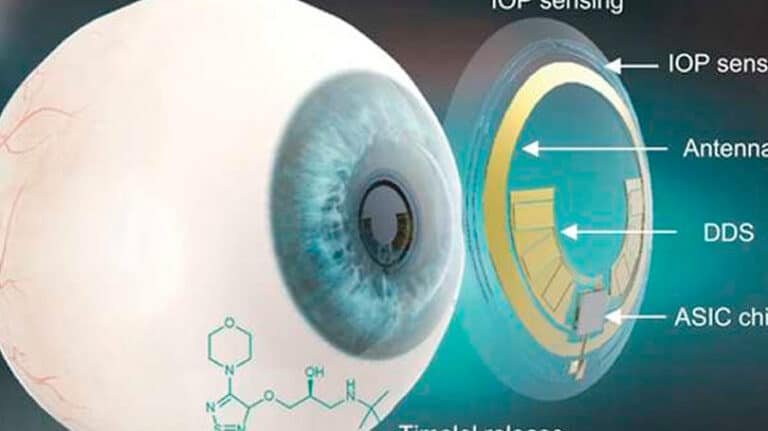

Los lentes de contacto inteligentes para medir la presión intraocular representan un avance revolucionario en el campo...